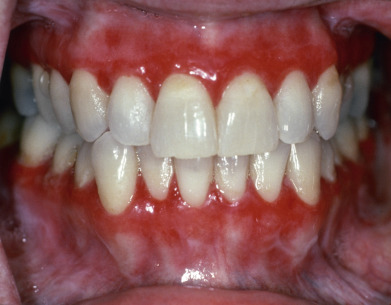

Oral mucosal LP is the most common form of mucosal LP, and it is usually chronic. Between 10% and 15% of patients with oral LP will also have skin lesions. Women represent 50%–75% of patients with oral LP. Oral LP in women begins 10 years later than in men (age 57 vs. 47). Oral lesions may be reticulate (reticular), the oral version of Wickham striae ( Fig. 12.8 ), erythematous (atrophic), or ulcerative (erosive) ( Fig. 12.9 ); lesions are often bilateral and symmetric. The most common pattern in oral LP is the ulcerative form (40% of patients). Usually, reticulate and erythematous lesions are found adjacent to the ulcerative areas. The erythematous pattern is the predominant pattern in 37% of patients, but almost always, reticulate lesions are also seen in these patients. In oral LP, the “classic” reticulate lesions are most prominent in 23% of patients. Rarely patients may have a white plaque mimicking leukoplakia, bullous, or papular lesions. Symptoms are least common in patients with reticulate lesions; 23% are symptomatic, and then only when the tongue is involved. All patients with erosive lesions are symptomatic, usually with burning or pain. Patients may simultaneously have several patterns, so patients are characterized by the primary form they exhibit. Lesions appear on any portion of the mouth, and multisite involvement is common. The buccal mucosa is involved in 90%, the gingiva in more than 50%, and the tongue in about 40%.

On the gingiva, LP may produce desquamative gingivitis (see Fig. 12.9 ). Gingival involvement is particularly difficult to diagnose and often requires biopsy for both histology and DIF to confirm the diagnosis and exclude other autoimmune causes of desquamative gingivitis. Gingival involvement is associated with accelerated gingival recession. Mechanical injury from dental procedures and poorly fitting appliances may trigger or exacerbate gingival LP. On the tongue and palate, lesions are often mistaken for leukoplakia. The lower lip is involved in 15% of oral LP patients, but the upper lip in only 2%. Lower lip LP is frequently mistaken for actinic cheilitis. Imiquimod treatment can lead to exacerbation of the labial LP, with extensive erosion and crusting. Oral LP is stable but chronic, with fewer than 3% of patients having a spontaneous remission in an average 5-year follow-up. Periodontitis appears to exacerbate oral LP, especially gingival disease. Plaque control either by the patient after training or by a dental professional improves the clinical appearance and pain.